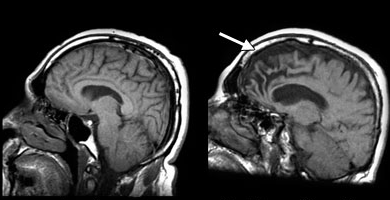

BUNAMA (DEMANS) NEDİR? Bunama (demans), kısaca beyni etkileyen bozuklukların neden olduğu bir grup etkinin bütünsel adıdır ama belirli bir hastalık değildir. Demansı olan insanlar giyinmek ya da yemek yemek gibi normal faaliyetlerde bulunmakta zorlanabilir. Sorunları çözme veya duygularını kontrol etme yeteneklerini kaybedebilirler. Kişilikleri değişebilir, aniden sinirlenebilirler veya orada bulunmayan şeyleri görebilirler.

Demans çok yaşlı insanlarda yaygın olmakla birlikte, yaşlanmanın doğal bir sonucu değildir. Bununla beraber demansın görülme sıklığı 50 yaşından sonra artar ve demans hastalığı ağır ilerleyen bir sürece sahiptir.

Hafıza kaybı, bunamanın ortak bir semptomudur. Bununla birlikte, tek başına hafıza kaybı demansınız olduğu anlamına gelmez. Demans hastaları, hafıza ve dil gibi iki veya daha fazla beyin fonksiyonuyla ciddi sorunlar yaşar.